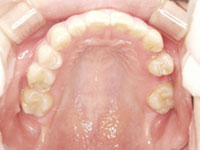

口内写真

口内写真とパノラマレントゲンを撮影し、まずは顎の骨の状態まで詳しく確認しました。.

・歯がない期間が長く続いたため隣の歯が横に倒れてしまい、歯と歯との間に隙間が2ケ所できてしまっていた。

歯がない期間が長く続いたため隣の歯が横に倒れてしまい、歯と歯との間に隙間が2ケ所できてしまっていたため、インプラントの前に矯正治療で隙間をなくす治療を行う